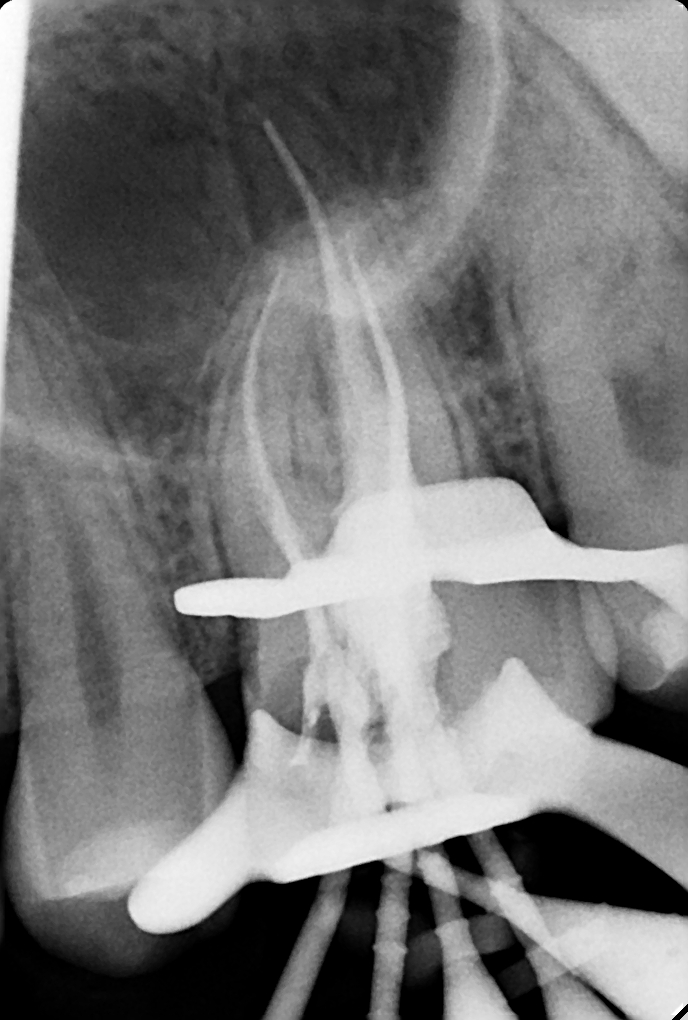

Клинические случаи в эндодонтии